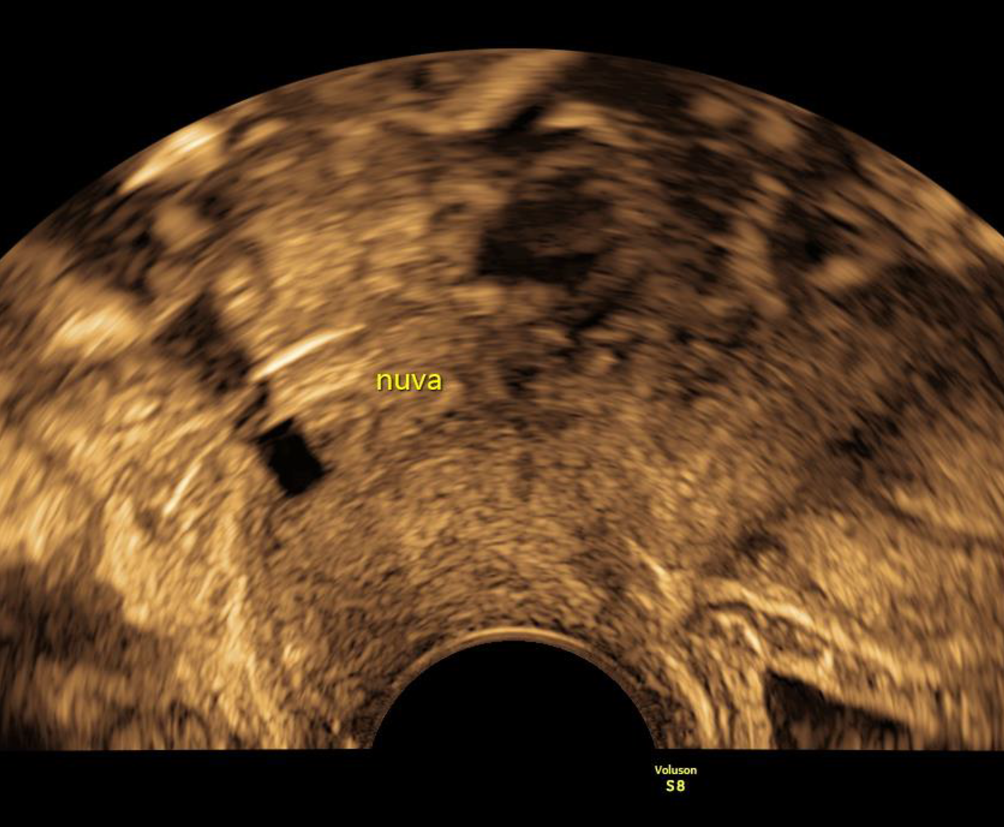

Abb. 7

Ein NuvaRing imponiert als rechteckiger, echoarmer Block unmittelbar hinter der Zervix

NuvaRing

Zum Abschluss sollte noch der NuvaRing erwähnt werden, der ein charakteristisches sonographisches Erscheinungsbild aufweist – im normalen Schnittbild hat er eine nahezu rechteckige Form, hinter der ein Schatten liegt, wie man ihn von Hormonspiralen kennt (Abb. 7). Es gibt Fallberichte von Anwenderinnen, die den NuvaRing versehentlich in der Harnblase platzierten, dieser kann mit entsprechend gefüllter Blase im Ultraschall gesehen und zystoskopisch entfernt werden [8].